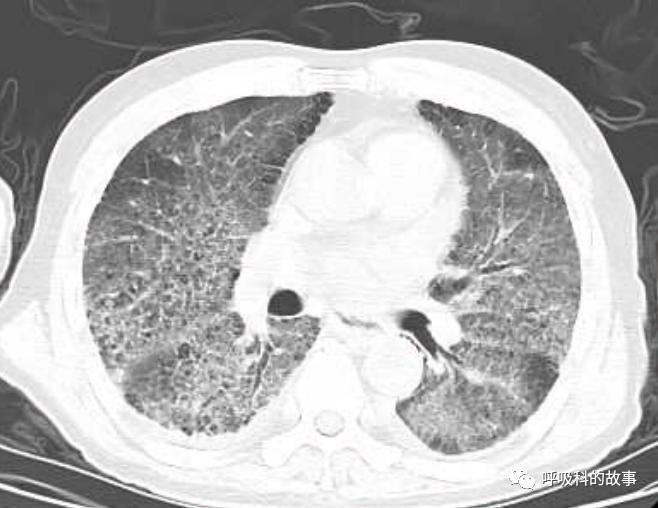

上周,我去会诊一个病人又出现了类似的情况,一个72岁的男性病人因为发生十二指肠球部溃疡穿孔入住我院胃肠外科,给予腹腔镜下十二指肠球部溃疡穿孔修补术。术后由于患者禁食就给予了大量的补液,大约有3000多毫升,其中0.9%氯化钠盐水(也就是我们通常所说的生理盐水)一共是补了接近2000ml,同时还补了1500ml的营养液呢。患者术后第二天晚上开始出现呼吸困难,程度进行性加重,到了术后的第五天,呼吸困难非常明显了,病人也出现端坐位呼吸,两肺出现严重的肺水肿转入ICU治疗。